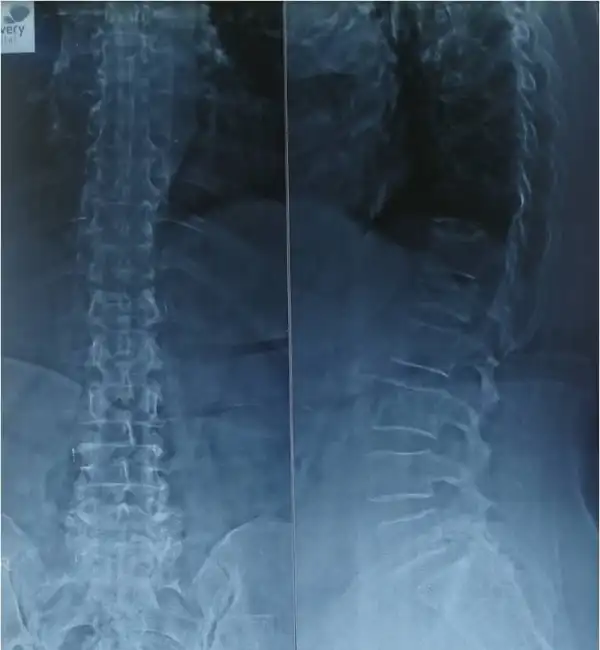

Pre Op Vertebroplasty

Post Op Vertebroplasty